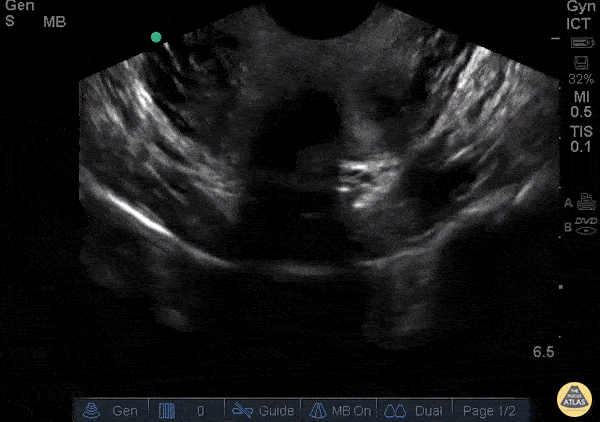

OB/Gyn - Bicornuate Uterus with IUP

WCUME 2017 Submission for "Best POCUS" 23 y/o female, pelvic pain, no vb or discharge, g1p0 found to be pregnant at this ER visit. Approximately 4 weeks by dates. Found to be pregnant and found to have a bicornuate uterus with IUP on the right side. Carl Alsup, MD - Sierra Nevada Memorial Hospital